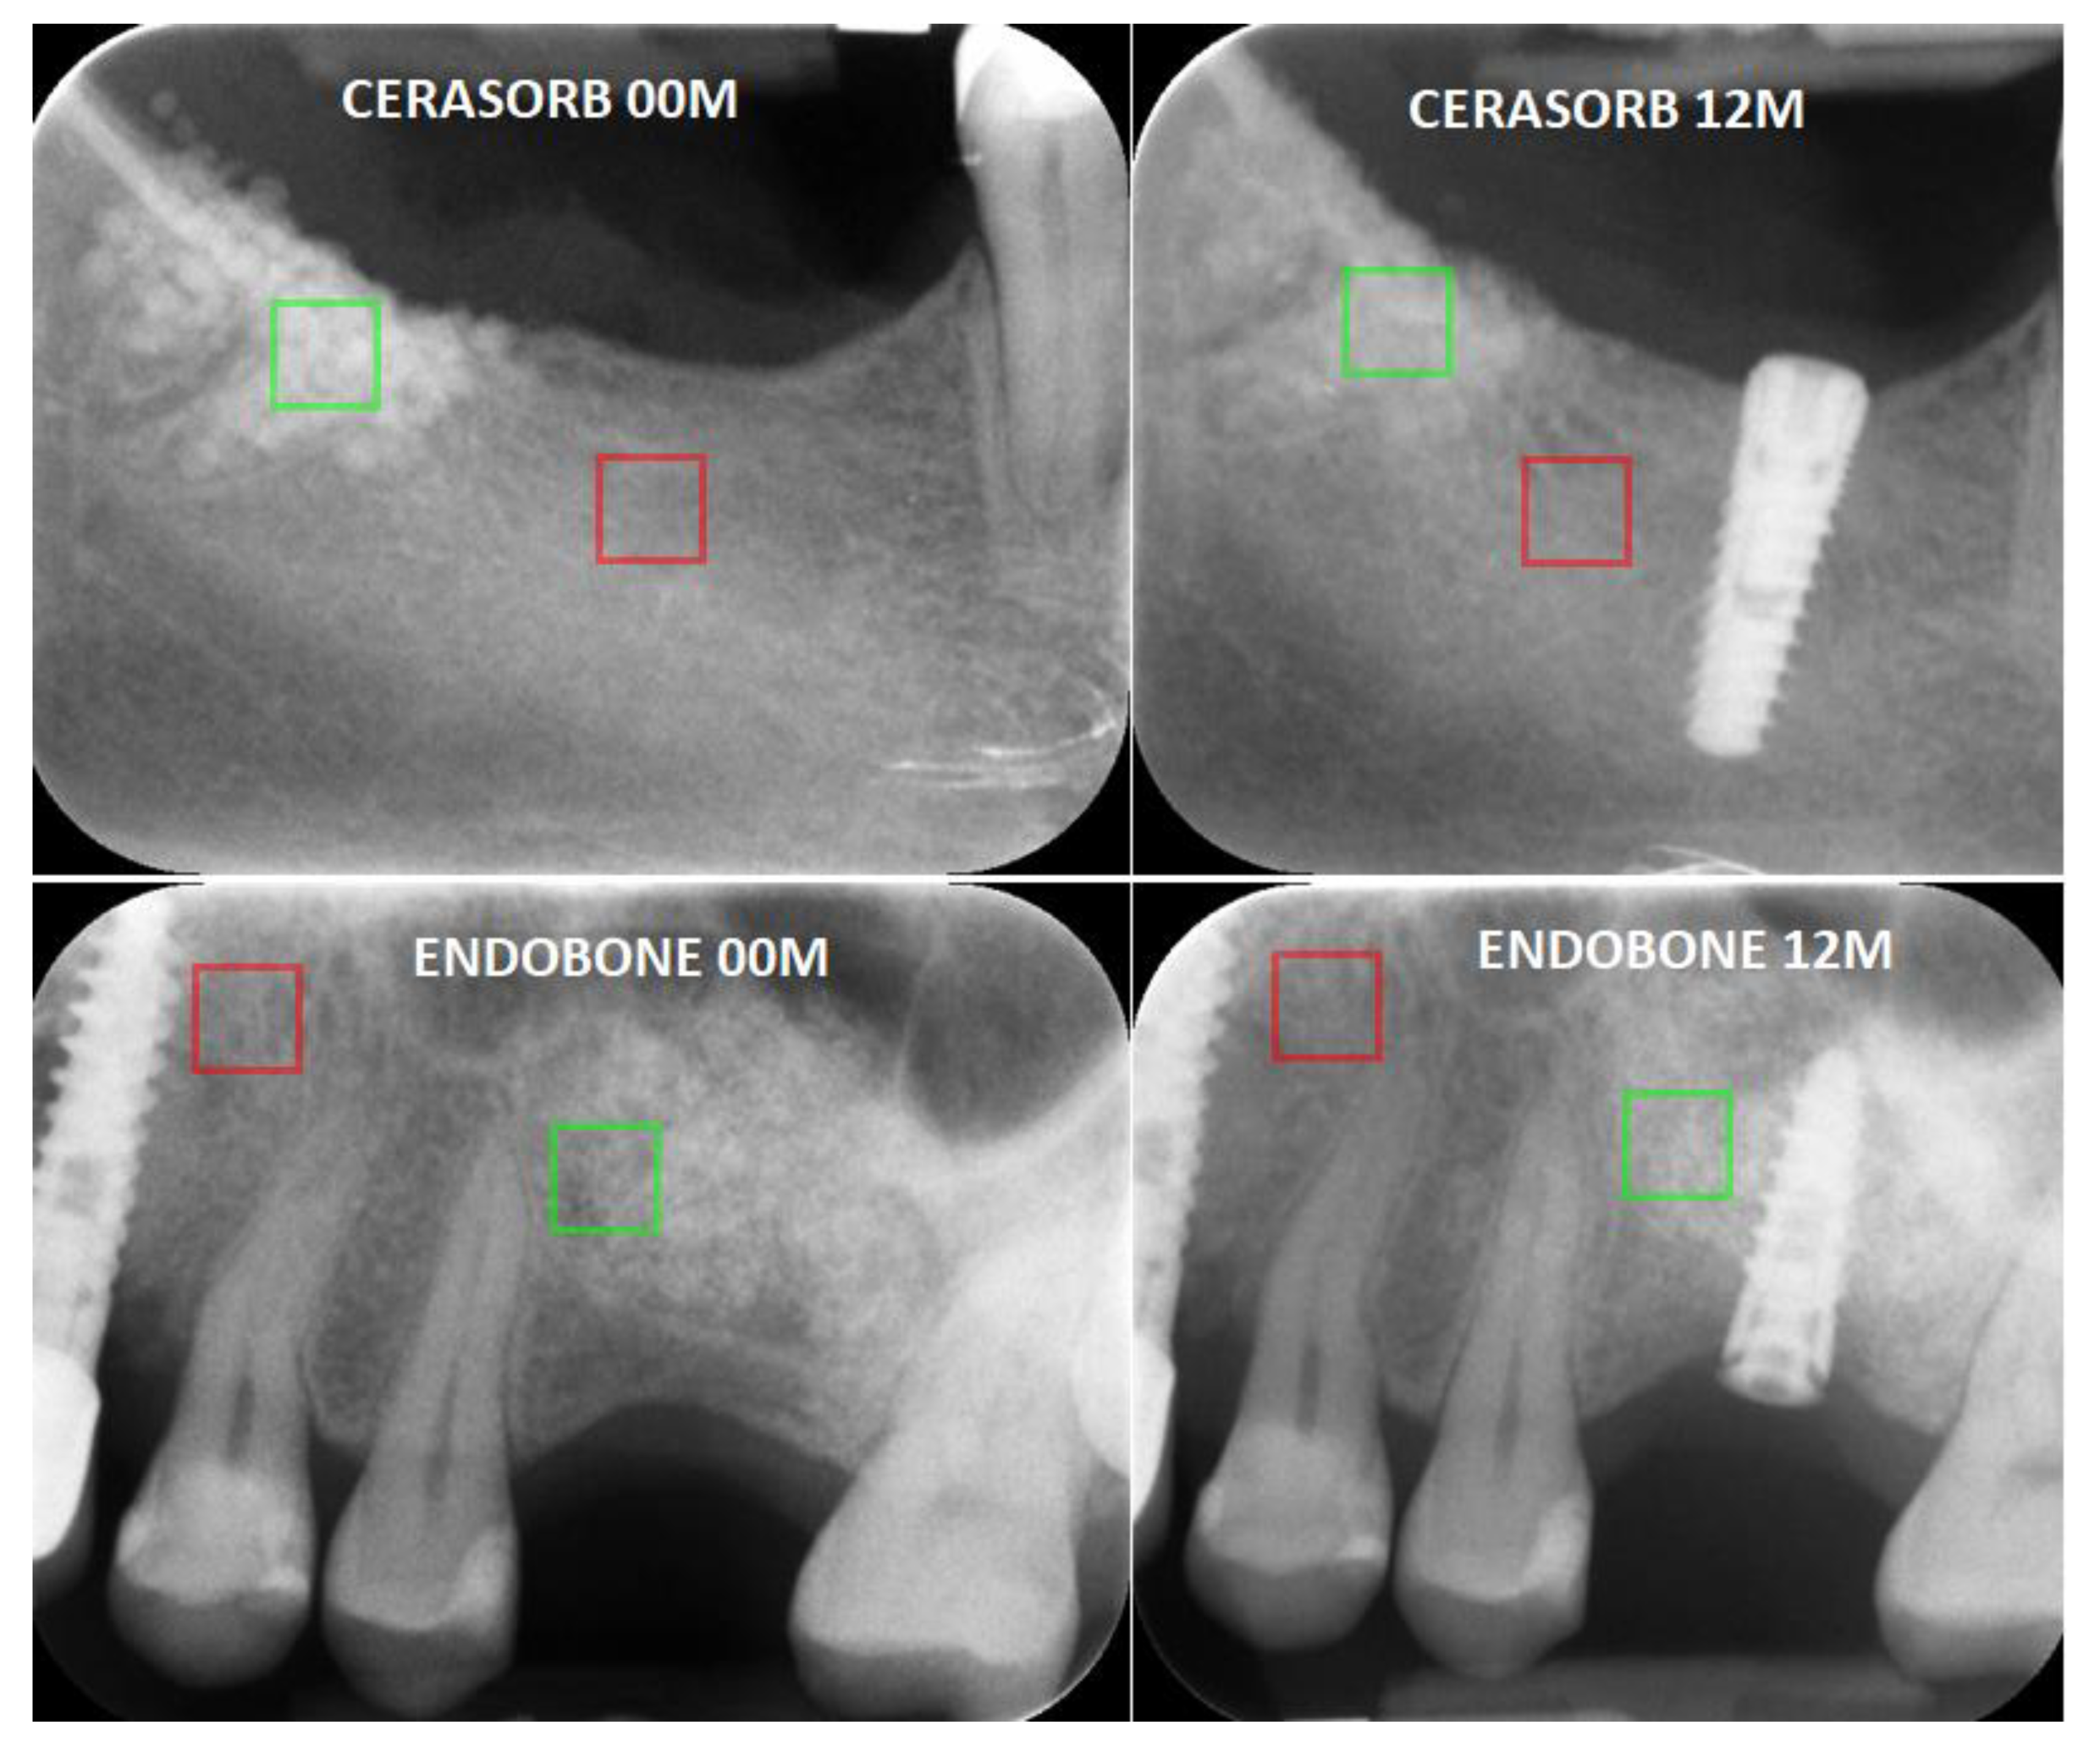

2. Materials and Methods

- High-rate resorbable: β tricalcium phosphate (Curasan: Cerasorb M, Wake Forest, NC, USA);

- Low-rate resorbable: hydroxyapatite (Zimmer Biomet Dental: Endobone, Palm Beach Gardens, FL, USA).